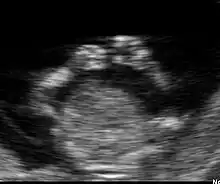

Embryon à 6 semaines